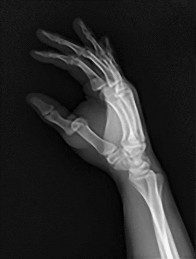

- الأشعة السينية (X-rays): هي الخطوة الأولى في تقييم الكسور، الخلوع، وتغيرات التهاب المفاصل. تساعد في تحديد مدى تدهور العظام والمسافات المفصلية. على سبيل المثال، تُظهر صور الأشعة السينية كسور السلاميات

أو كسور قاعدة العظم المشطي الخامس

، بالإضافة إلى علامات مثل "الدمعة الشعاعية" (Radiographic Teardrop) في الرسغ التي تمثل الزاوية الزندية الراحية الحرجة للكعبرة البعيدة

. - الأشعة المقطعية (CT Scan): توفر صوراً تفصيلية ثلاثية الأبعاد للعظام، وهي مفيدة جداً لتقييم الكسور المعقدة، مثل كسور العظم الخطافي (Hamate Hook Fracture) التي قد لا تظهر في الأشعة السينية العادية